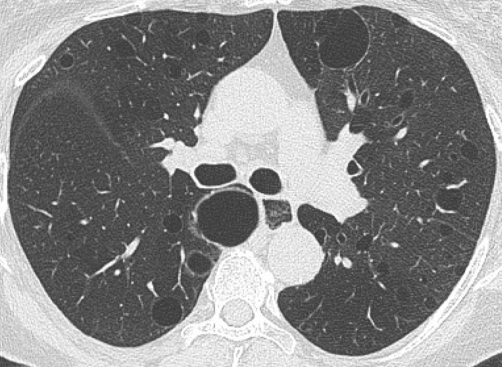

- Verre dépoli, à distance de la fibrose (du VD sur la fibrose = probable fibrose microscopique)

- Réticulations sous-pleurales bilatérales

- Bronchiectasies de traction

- Pas de rayon de miel (ou rare)

- Epargne Sous pleurale (spécifique++ mais vu que dans 30% des cas, surtout au stade précoce)